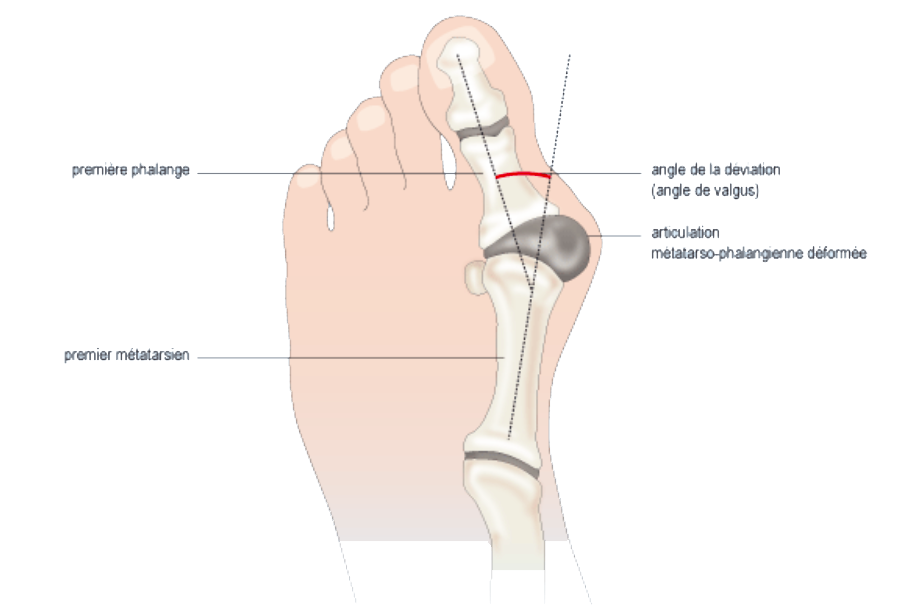

Hallux Valgus

L’hallux valgus, ou « oignon » au pied, est une déviation vers l’extérieur du gros orteil. Il est favorisé par plusieurs facteurs comme l’hérédité, l’âge, ou le port de chaussures à talons hauts et à bouts étroits. L’hallux valgus est souvent douloureux lorsque la déformation devient importante.

En l’absence de traitement, l’hallux valgus évolue vers l’aggravation de la déformation.

Avant d’envisager une chirurgie, l’orthésiste réalise des orthèses plantaires sur-mesure. Elles seront finement réglées de manière à limiter la déformation.

Un redresseur d’orteil à port nocturne peut également être envisagé. Il permet de soulager l’articulation en positionnant l’orteil dans sa colonne naturelle.